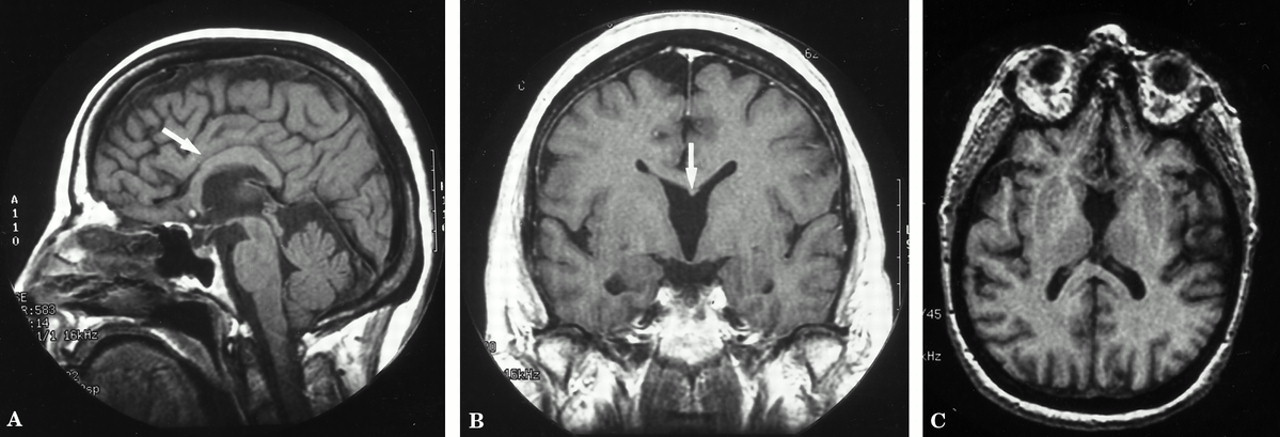

核磁共振大脑扫描显示基底前脑畸形的许多特性。有异常配置和发育不全的膝,城楼上,和胼胝体压部,前连合的发育不全,缺乏透明隔和列的穹窿。5毫米高的焦点T1信号只是前胼胝体的讲坛上不存在脂肪抑制图像(图中未显示)是自然的不确定,但可能代表一个皮样的。斜改革从3 d被宠坏的梯度回波序列表现出异常的灰质在后下额叶前部的胼胝体发育不全的膝与异常相关的配置额侧脑室和第三脑室前角(图2)。减法SPECT成像显示轻度减少吸收在左颞叶前部。